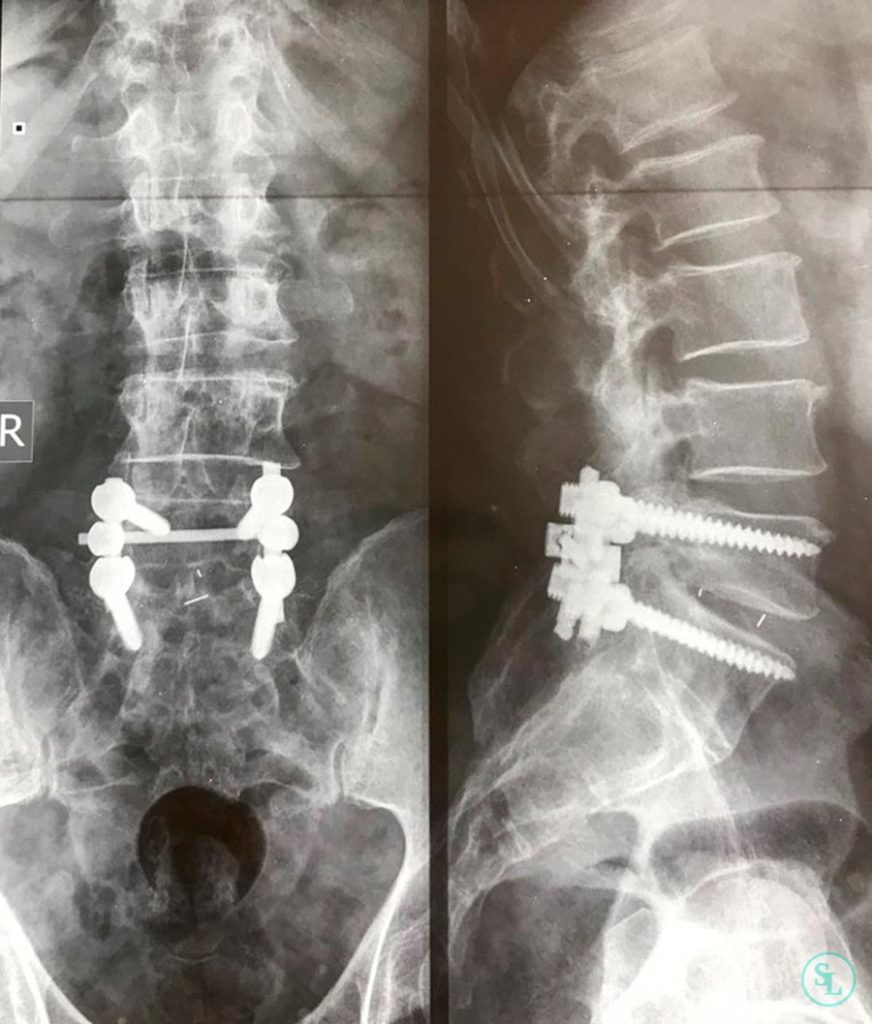

- Устанавливают опорно-стабилизирующие системы (при необходимости).

Стабилизирующие конструкции

Удаление тел, их отростков и других анатомических структур чревато дестабилизацией подвергшегося вмешательству позвоночно-двигательного сегмента, а также повышению риска развития тяжелых прогрессирующих кифотических и сколиотических деформаций. Причем чаще страдает поясничный и шейный отдел, а также в переходные зоны.

Это обуславливает необходимость часто использовать на завершающем этапе операции методики фиксации позвонков. Особенно они важны при выполнении ламинэктомии у детей и подростков, поскольку в таких случаях ситуация усугубляется асимметричным ростом позвонков.

Одним из способов стабилизации прооперированного позвоночно-двигательного сегмента является спондилодез. Его выполнение подразумевает установку специальных опорно-стабилизирующих конструкций, прочно соединяющих соседние позвонки в области воздействия между собой. В определенных случаях дополнительно требуется провести трансплантацию взятого у пациента из подвздошной кости фрагмента. В результате позвонки плотно срастаются между собой и теряют способность двигаться. Но при проведении ламинэктомии на 1 или 2 позвонках и их спондилодезе пациенты обычно не замечают существенных ограничений при движениях.

Современная медицина располагает металлоконструкциями различных типов, что позволяет проводить эффективную стабилизацию. Причем многие из них способны монтироваться таким образом, что в дальнейшем по мере роста ребенка их можно будет удалить.

Стабилизация позвонка при ламинэктомии